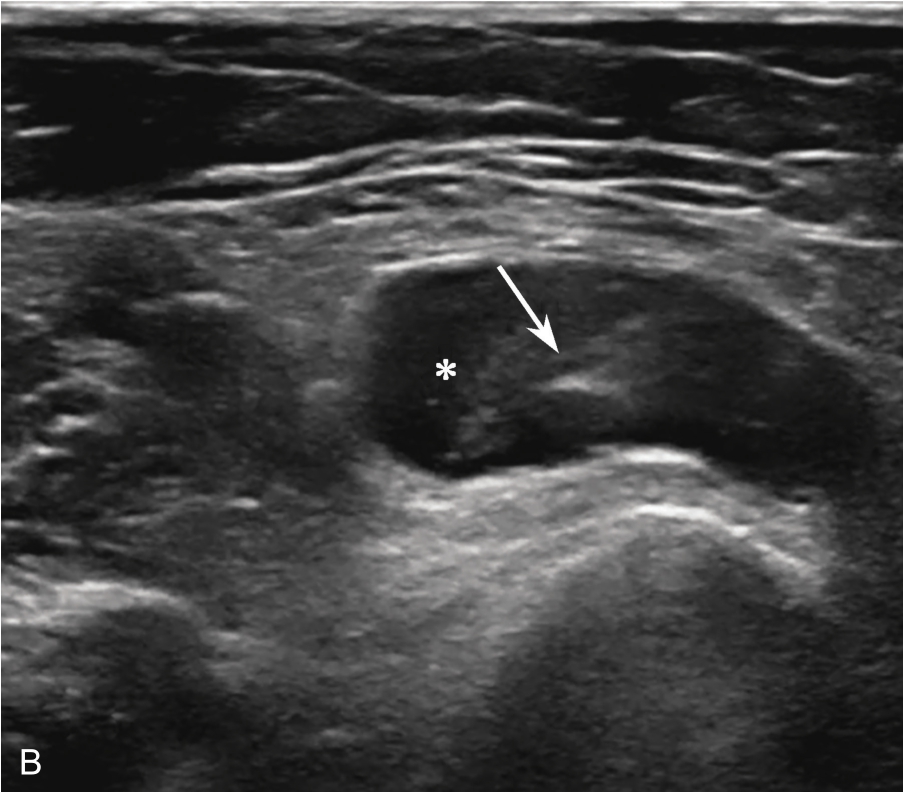

3.当肩袖回声不均匀,有可疑的滑囊面撕裂或全层撕裂,行超声引导下肩峰下-三角肌下滑囊造影检查,可提高对肩袖撕裂的诊断率。方法:将2~5ml生理盐水与0.5ml的超声造影剂混合后,注入肩峰下-三角肌下滑囊,无撕裂的滑囊呈线状高增强(图2-1-8),肩袖滑囊面部分撕裂可见造影剂混合液从滑囊进入肩袖肌腱内而未达肱骨头表面(图2-1-9),若观察到其进入肩关节腔或肱二头肌长头腱鞘,则诊断肩袖全层撕裂(图2-1-10)。

▲ 图2-1-8 超声引导下肩峰下-三角肌下滑囊造影图(一)

A.超声引导下滑囊内注入超声造影剂后,滑囊呈线状高增强(箭头);B.注入造影剂后的滑囊(箭头),冈上肌腱(SUP)连续性好,未见撕裂,HH:肱骨头